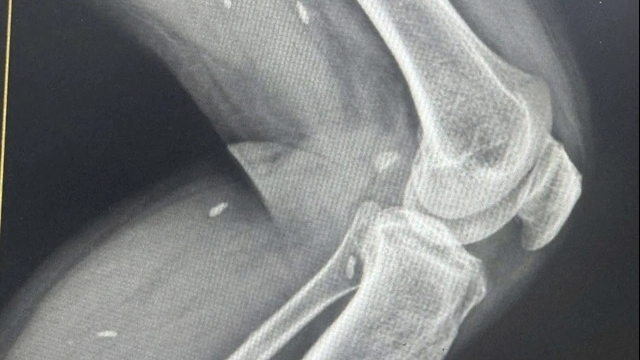

Ngay sau khi bệnh nhân vào Khoa Cấp cứu, Bệnh viện Trung ương Quân đội 108, các bác sĩ lập tức tiến hành hồi sinh tim phổi nâng cao, điện tim có hình ảnh rung thất. Bệnh nhân đã được sốc điện khử rung nhiều lần. Sau 12 lần sốc điện kết hợp dùng thuốc tích cực, bệnh nhân đã có tuần hoàn tự nhiên.

Thạc sĩ Phạm Quang Trình, Bệnh viện Trung ương Quân đội 108 - người trực tiếp cấp cứu cho bệnh nhân nhận định: "Bệnh nhân bị ngừng tim do tăng kali máu, kết hợp sốc nhiễm khuẩn do viêm phổi, nhồi máu phổi trên nền viêm phúc mạc do vỡ tá tràng đã phẫu thuật ngày thứ 13. Tình trạng bệnh nhân rất nguy kịch".

Sau khi được cấp cứu ngừng tuần hoàn thành công, bệnh nhân được chuyển sang Khoa Hồi sức ngoại, lọc máu liên tục, thở máy, chống đông, kháng sinh mạnh toàn thân và điều trị tích cực.

Tới ngày 28/6, sau gần một tuần điều trị, bệnh nhân phục hồi hoàn toàn, không để lại bất cứ di chứng thần kinh nào.

| Tăng kali máu là nồng độ kali huyết thanh trên 5,5 mmol/L, thường là kết quả của giảm bài tiết kali của thận hoặc dịch chuyển kali bất thường ra khỏi tế bào. Một vài yếu tố đóng góp đồng thời gây ra tình trạng này, bao gồm tăng lượng kali nhập vào, thuốc làm thận giảm bài tiết kali, tổn thương thận cấp tính hoặc bệnh thận mạn tính. Tăng kali máu cũng có thể xảy ra trong tình trạng toan chuyển hóa (ví dụ: Toan ceton đái tháo đường). Các biểu hiện lâm sàng nói chung là thần kinh cơ, dẫn đến yếu cơ và độc tính lên tim, khi nặng, có thể tiến triển thành rung thất thoặc vô tâm thu. Rung thất dẫn tới sự mất đồng bộ liên tục của các sợi cơ tâm thất, làm mất các nhát bóp hiệu quả của tâm thất, không có giá trị bơm máu ra động mạch như co bóp thông thường. Rung thất khiến bệnh nhân ngất và tử vong ngay lập tức trong vài phút. Bệnh nhân cần được cấp cứu ngừng tuần hoàn, bao gồm khử rung thất ngay lập tức. |